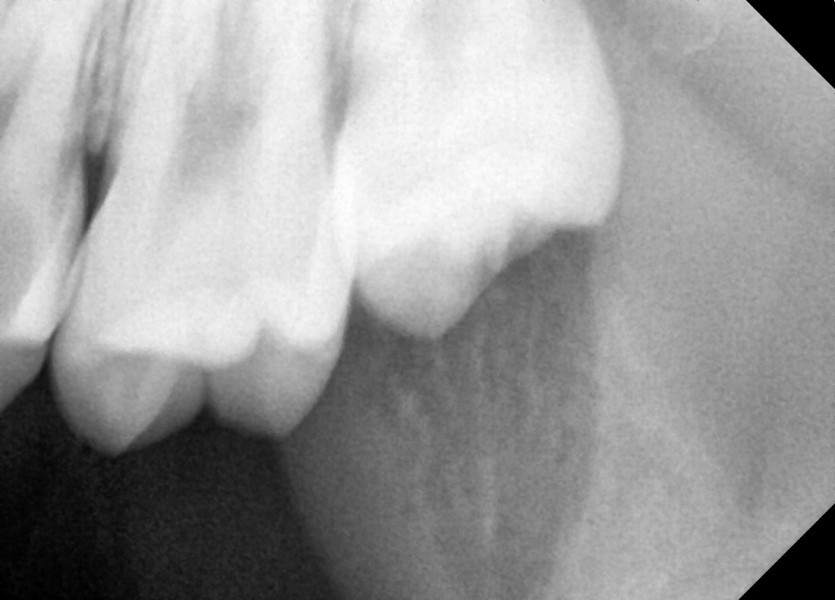

#28,38 사랑니 발치

구강 외과 전문의가 당일 발치했습니다.